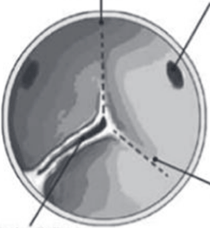

Before making any decisions, I ended up getting a CT scan of the heart in order to better see my heart and valve structure. This revealed that my valve is actually unicuspid rather than bicuspid. This means that all of the leaflets are fused, leaving just one opening:

The fact that my valve is unicuspid took the less invasive TAVR procedure off the table. This left me with two options: the Ross procedure (longer durability, comparable to normal heart lifespan, but more complex surgery) or a valve replacement with a pig or cow valve (less complex surgery, shorter durability of 10-12 years). Given the difference in durability, I decided to explore the Ross procedure, and go to one of the leading Ross specialists in the country at MGH.